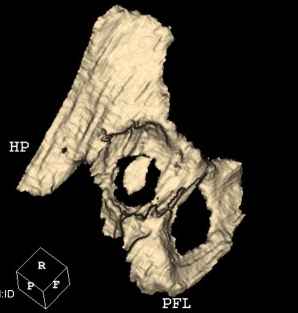

Мужчина, 45 лет. 6 мес. назад перенес тотальное эндопротезирование правого тазобедренного сустава по поводу ложного сустава шейки бедра.

Характер реконструкции вертлужной впадины не известен. Через 3 мес. после операции отметил щелчки и хруст при движениях в области эндопротеза. В анамнезе туберкулез легких. Сейчас, по заключению фтизиатра, в легких активного процесса нет. Местного воспаления нет.Предполагается нестабильность чашки в связи с бактериальным воспалением. Планируется удаление чашки и цемента, пластика дна измельченными аутотрансплантами и гидроксилапатитной керамикой, затем кольцо Мюллер, цементная чашка.

Смущает и ножка - зона просветления вокруг мантии. Предложения по тактике?

И еще, в случае одномоментного реэндопротезирования здесь показана имплантация кольца Бур-Шнайдера (ИМХО)

прямо скажем, очень загадочная конструкция с проволокой и винтами. :) На основании чего Вы подозреваете септическую нестабильность? Каковы результаты анализов? Согласен с доктором - нужно сделать пункцию. Есть ли снимки до и сразу после операции? Знаете ли Вы диаметр головки,какой будет внутренний диаметр Вашей чашки? Известно ли, чей протез? Может есть смысл найти автора работы и узнать о подробностях установки протеза?